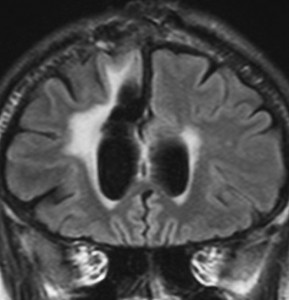

T2-FLAIR mismatch sign (T2とフレアの信号が違うこと)

protoplasmic astrocytomaに特徴的なMRI所見です。T2強調画像(左側)では白く(強い均一な高信号)見えます。でもフレア画像(右側)では白く縁取ったように見えます。びまん性星細胞腫の大きな特徴とされます。内部がとても柔らかいドロドロした腫瘍のこともあります。